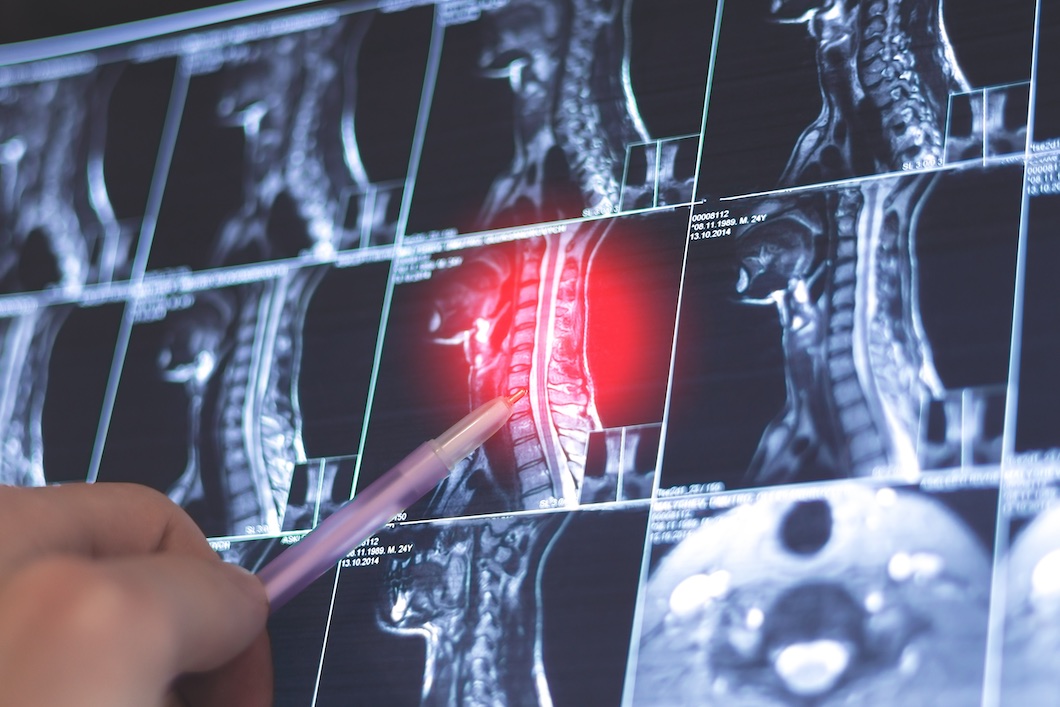

Axiale gewrichtspsoriasis gelijkt sterk op axiale spondyloartritis, maar vertoont toch een aantal specifieke radiografische en klinische tekenen. Beeldvorming toont over het algemeen asymmetrische syndesmofyten, vooral van de halswervels, en minder vaak een sacro-iliitis. Patiënten met een axiale PsA zijn ouder en klagen minder van inflammatoire rugpijn. Bij beide aandoeningen is er een overexpressie van de IL-23/IL-17-as. IL-23-antagonisten zijn niet effectief bij axiale spondyloartritis, maar zouden volgens recente studies wel werken bij een axiale gewrichtspsoriasis. Verder onderzoek is wenselijk om dat verder te documenteren. Hopelijk zal dat uitmonden in een beter inzicht in axPsA en een betere behandeling.